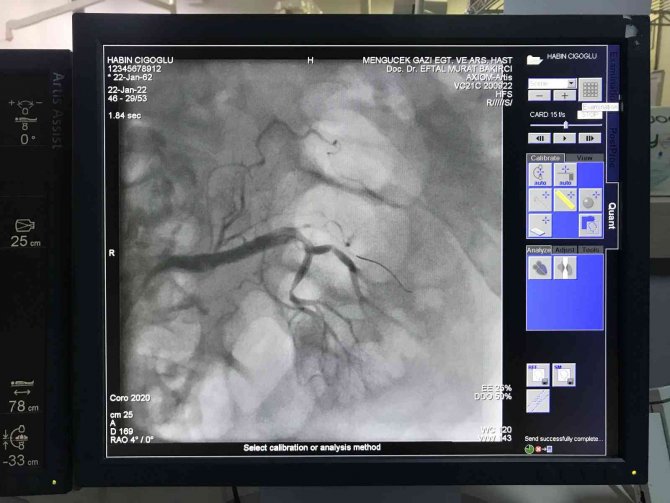

Erzincan Mengücek Gazi Eğitim ve Araştırma Hastanesinde böbrek damarına anjiyo işlemi ilk defa uygulandı.

Erzincan'da şiddetli karın ağrısı ve kusma şikâyetleri ile hastaneye giden Habib Cigaoğlu'nun böbrek atardamarında tıkanıklık olduğu tespit edildi. Çok nadir görülen vaka hastane doktorları tarafından Erzincan'da ilk kez uygulanacak bir yöntemle tedavi edildi. Hastanın böbrek damarına tıpkı kalp damarlarına yapıldığı gibi anjiyo işlemi uygulandı. Yapılan işlem Erzincan'da stent tedavisi ile düzeltilebilen ilk vaka olarak kayıtlara geçti. Çevre illerde de çok nadir görülen hastalık ve tedavi yönteminde, Erzincan Mengücek Gazi Eğitim ve Araştırma Hastanesi hekimleri tarafından başarıyla gerçekleştirildi.

Hastayı başından beri takip eden ve anjiyo işlemini diğer doktorlarla beraber uygulayan Kardiyoloji Anabilim Dalından Doç. Dr. Hüsnü Değirmenci, sık karşılaşılan bir durum olmadığını lakin hastalar tarafından da korkulacak bir tedavi yöntemi olmadığını belirterek, "Çok nadir gördüğümüz, bin vaka da, bin hasta da bir kişi de gördüğümüz bir hastalık. Böbrek atardamarının pıhtı ile tıkanmasını çok fazla görmüyoruz. Çok nadir görülüyor. Bu işlemin bizim için önemli olan yanı, Erzincan'da bu şekilde stent tedavisi ile ve etkili tedavilerle düzeltilebilen ilk vakadır. Hasta bize şiddetli karın ağrısı ve kusma şikâyetleriyle geldi. Enfeksiyon değerleri yüksekti. Biz hastaya hemen ilaç tedavisi, medikal tedavi başladık. Takibinde de karın damarlarını görüntüleyen, böbrek atardamarını görüntüleyen bir tomografi istedik. Tomografi de böbrek damarında kanlanmanın olmadığını görünce hastaya acil işlem yapma kararı aldık. Yaptığımız işlemde Prof. Dr. Eftal Bakırcı ile beraber uyguladık. Hastamıza riskler anlatılarak anjiyografi ünitesine aldık. Anjiyografi ünitesine hastaya özel malzemeler kullanarak balon ve ilgili kateter dediğimiz malzemeleri kullanarak bu işlemi gerçekleştirdik. Hastanın ağrısı henüz masadayken geçti. Takip eden günlerde de servise alındı hastamız ve orada böbrek doktorlarımız, nefroloji uzmanları, enfeksiyon hastalıkları uzmanlarının da desteğiyle hastamız tedavi olarak tam şifa ile hastanemizden ayrılmış oldu. Bu işlem gerçekten bizim aşina olduğumuz bir işlem değildi. Ancak biz bu işlemi kalp-damar tıkanıklıklarında yaptığımız için, böbrek atardamarı gibi büyük damarların işlemleri bizim için zorluk oluşturmamakta. Böyle bir vaka olması durumunda hastalarımızın, halkımızın endişe etmesine gerek yok. Erzincan Kardiyoloji Kliniği olarak genç ve dinamik bir kadro ile birlikte çalışıyoruz. Burası gerçekten oturmuş bir klinik olarak Erzincan halkına ve bölge halkına hizmet vermektedir" diye konuştu.